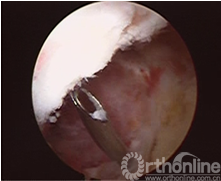

患者取仰卧患膝屈曲90°位,连续硬膜外麻醉,患肢大腿根部上气囊止血带,70Kpa,重力关节灌洗液悬挂在高于术膝1.2m处,常规前内、前外侧入路置入关节镜及工具。行关节镜常规入路清除关节内积血及凝血块,确诊交叉韧带撕脱骨折,处理半月板等其他损伤,仔细清理骨床及撕脱骨块。胫骨髁间隆突前区的骨折,应仔细清除血凝块及游离碎骨块,用关节镜刮勺略加深胫骨侧骨创面(图1)。陈旧性骨折不愈合的病例需使骨折面的两面新鲜化。撕脱骨片已前翘畸形愈合的病例需使愈合的后端再骨折并使创面新鲜化。

图1 图2